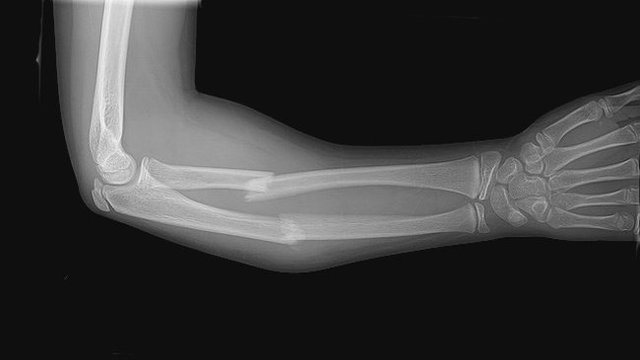

• Mi primer fractura xP

Mi primer fractura xP

Me fracture el brazo derecho x´D